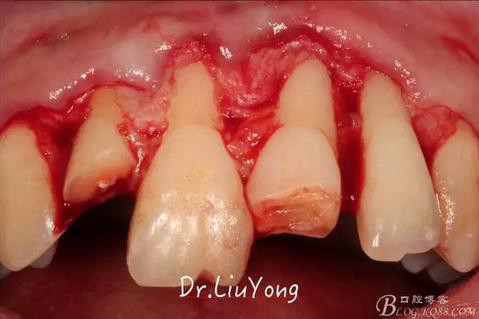

術(shù)中,可見(jiàn)明顯的唇側(cè)骨開(kāi)裂,如上圖